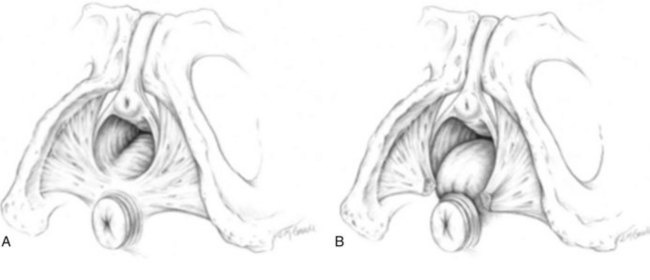

The posterior vaginal compartment comprises the peritoneum of the cul-de-sac, the rectum, and the perineum. Defects in the rectovaginal fascia either in the form of attenuated fascia or site-specific tears will result in herniation of the rectum and sometimes the small bowel into the vagina. Rectoceles may be divided into low, midvaginal, or high depending on the location of loss of support, and it may present as a combination of defects. Richardson was the first to describe site-specific defects of the rectovaginal fascia in 1993 (Fig. 72–9). Defects in the cardinal/uterosacral ligament complex can result in high rectoceles and can involve enteroceles. Enteroceles are estimated to be present in 0.1% to 16% of women undergoing surgery for POP (Chou et al, 2000). Loss of support in the mid vagina from the lateral attachments to the arcus tendineus fascia rectovaginalis will result in a bulging in the midportion of the posterior compartment. The perineal body is suspended from the sacrum by the contiguous support of the uterosacral ligaments and rectovaginal septum. Any break in this support system will lead to a hypermobile perineal body that descends with increases in intra-abdominal pressures (Richardson, 1993). Separation of the perineal body at the level of the rectovaginal fascia results in perineal descent or a low rectocele. The rectocele will be visible just inside the hymen posteriorly (Fig. 72–10). If perineal body detachment is left untreated at the time of rectocele repair, a perineal rectocele can occur in which the rectum bulges into the perineal body, termed a perineal rectocele (Richardson, 1995).